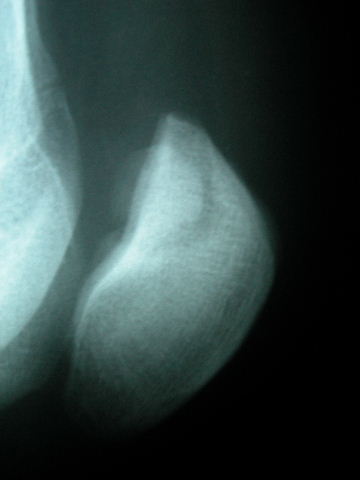

Densitometría en calcáneo